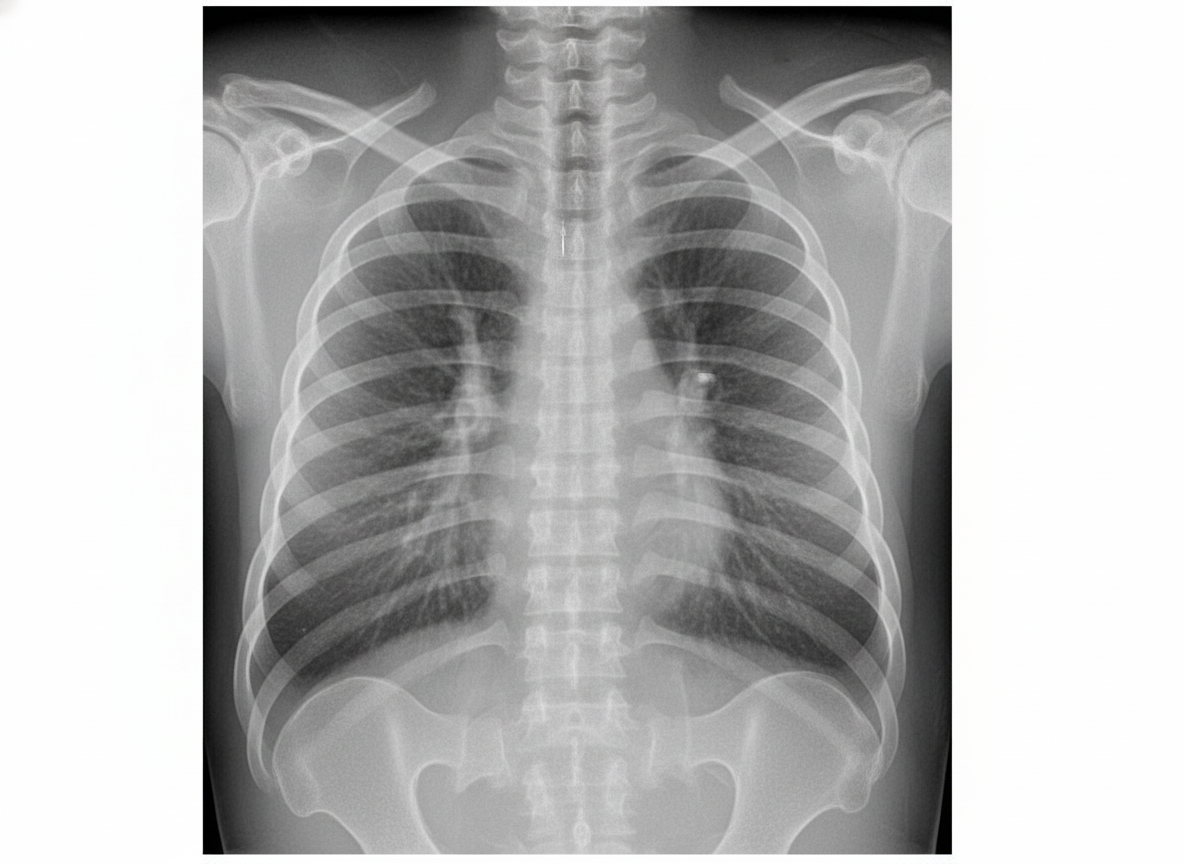

Explanation: ***Supportive care as it resolves spontaneously*** - **Transient Tachypnea of the Newborn (TTN)** is caused by **delayed clearance of fetal lung fluid** and typically resolves within 24-48 hours without specific intervention. - Management involves **observation**, **oxygen supplementation** if needed, and ensuring adequate **fluid intake** while avoiding overhydration. *Oxygen delivery by CPAP* - **CPAP** is primarily indicated for **Respiratory Distress Syndrome (RDS)** or other conditions requiring **positive pressure ventilation**. - TTN rarely requires CPAP as it responds well to **minimal oxygen support** and **conservative management**. *Surfactant provided by InSURre technique* - **Surfactant therapy** is specifically indicated for **RDS** caused by **surfactant deficiency**, typically in preterm infants. - TTN involves **fluid retention** rather than surfactant deficiency, making surfactant therapy **ineffective** for this condition. *Oxygen delivery by endotracheal intubation* - **Endotracheal intubation** is reserved for severe respiratory failure requiring **mechanical ventilation** support. - TTN presents with **mild respiratory distress** and rarely progresses to require invasive ventilatory support.